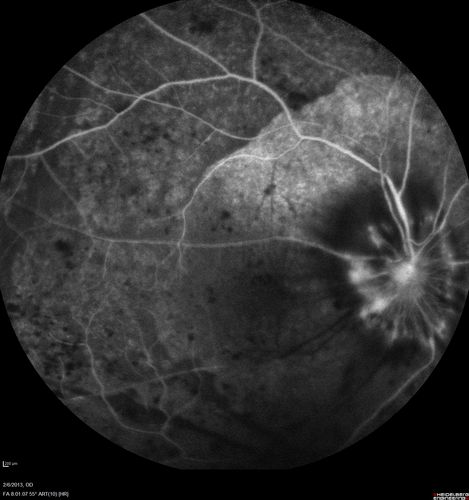

Vasculitis - Retinitis - Uveitis - Vision NLP right eye , 20/50 left eye

Unknown - Possible Syphilitic